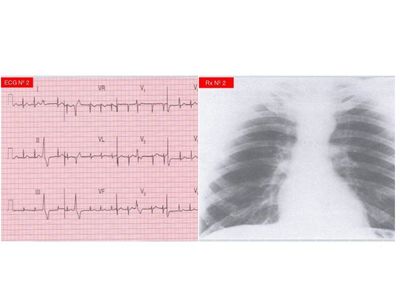

El siguiente test permite que estudiantes de medicina practiquen sus habilidades de diagnóstico médico en la cual se presentan casos médicos reales donde los estudiantes deben diagnosticar al paciente de acuerdo a una serie de alternativas

Destacado quiz sobre electrocardiograma. Pon a prueba tus habilidades de diagnóstico médico con estos ejercicios basados en casos reales. Al finalizar corrobora tus respuestas.

Test Electrocardiograma